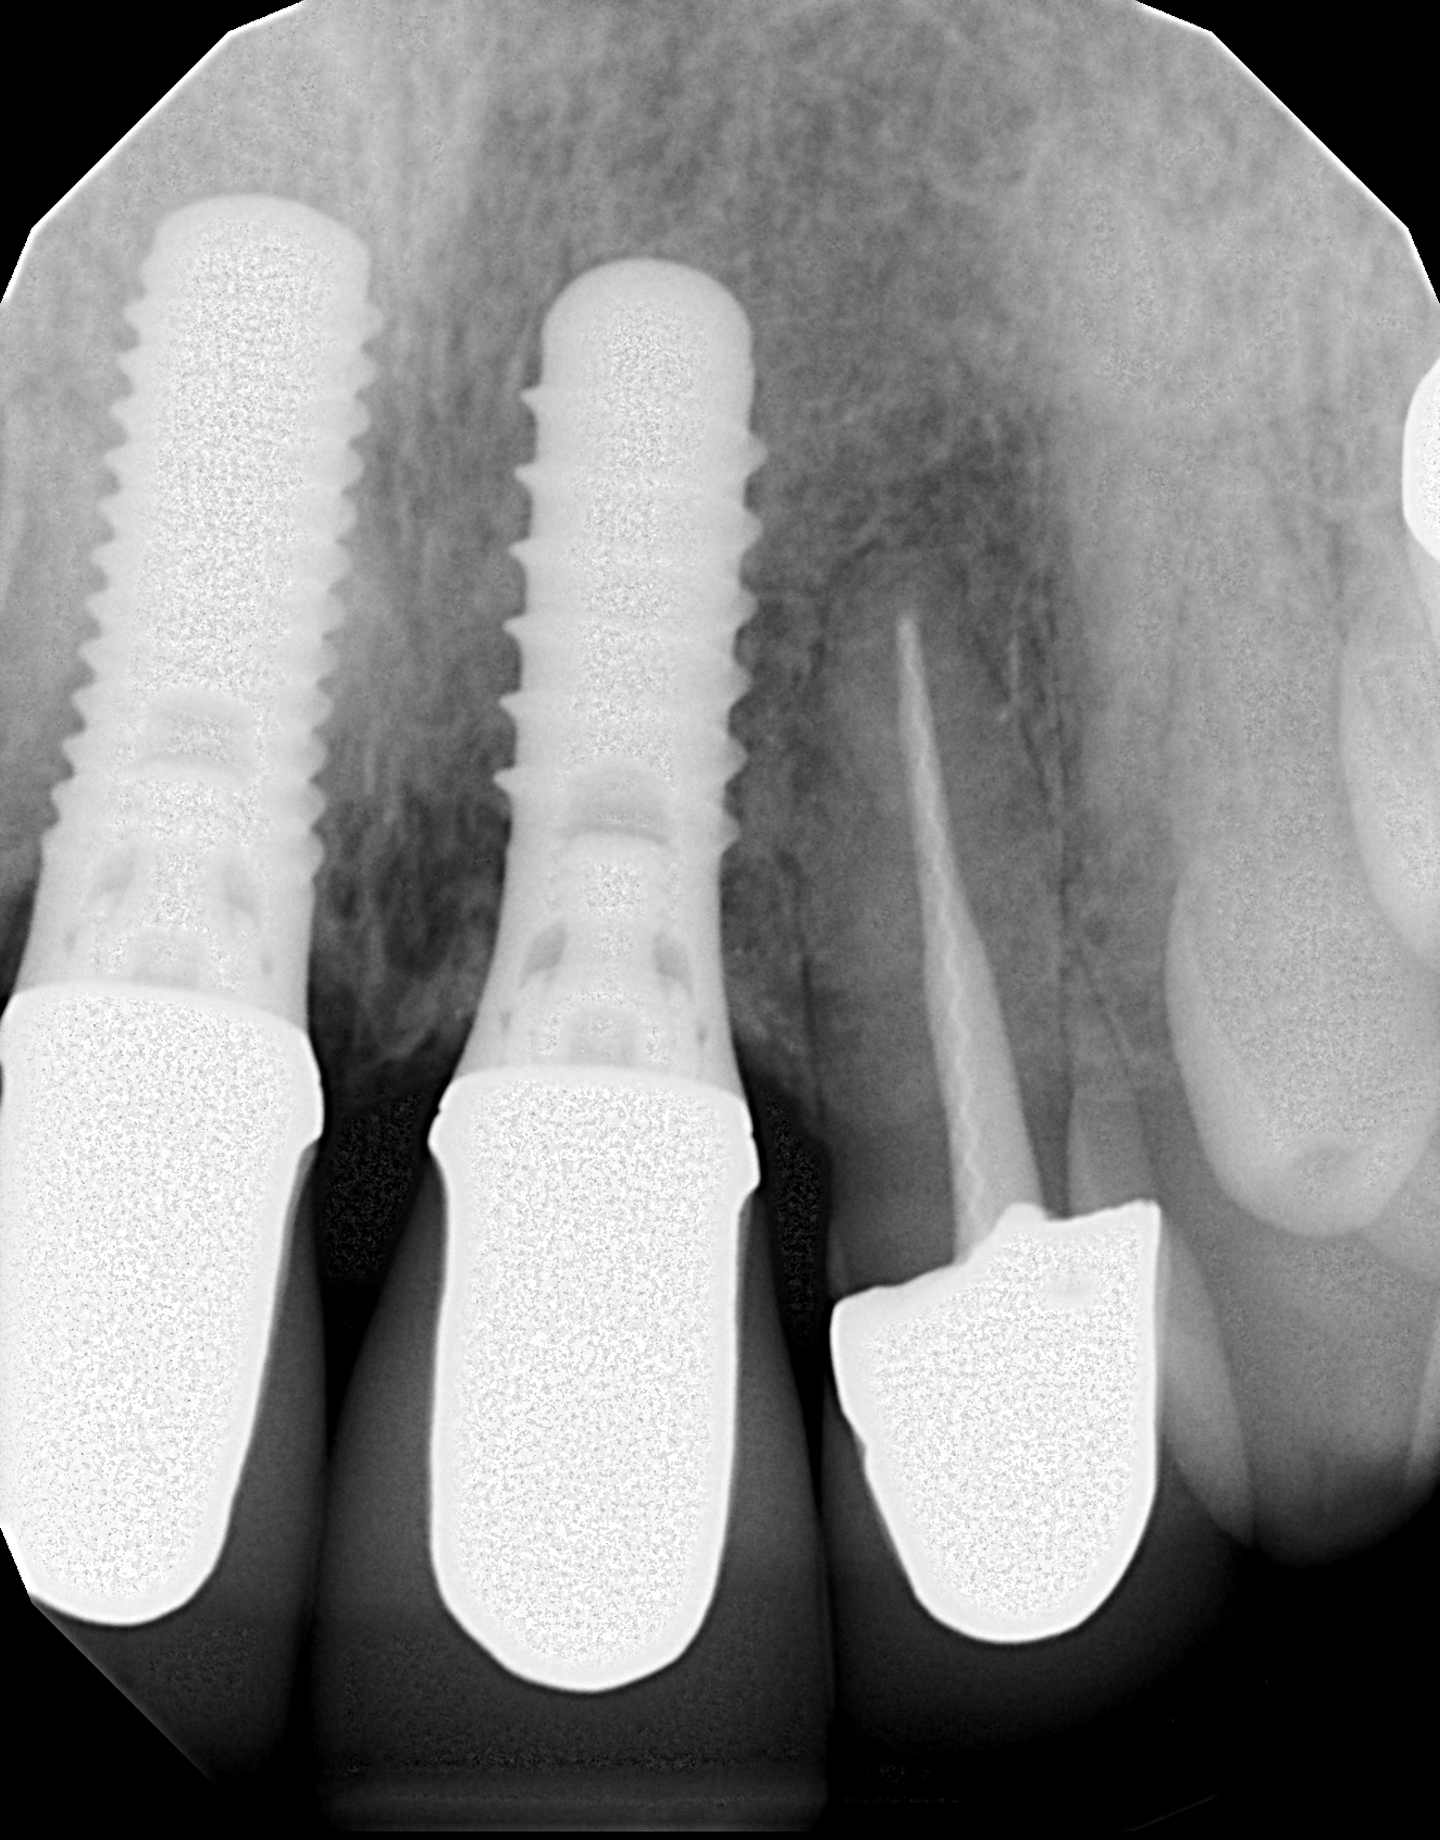

Managing Patients with a Loose Implant Abutment Screw jcda

Figure 1 from FACTORS AFFECTING THE ABUTMENT SCREW LOOSENING Semantic Dental Implant Screw Keeps Coming Loose Let’s understand why abutment screws loosen and how to fix the dreaded issue. Or, maybe the screw is broken. If left loose, the screw could break, and damage could be done to the screw, the. Loose dental implants can be a concerning issue, but they can be effectively managed with prompt diagnosis, appropriate treatment, and preventive measures. Occlusion can play. Dental Implant Screw Keeps Coming Loose.